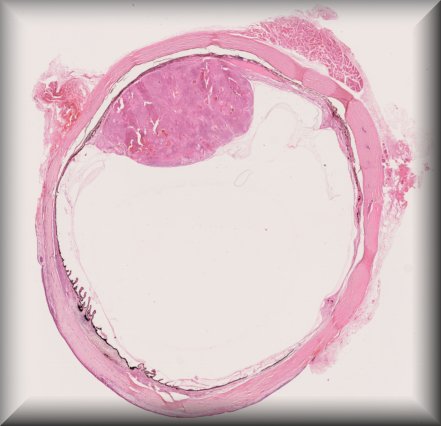

Claudia Auw-Haedrich (Freiburg): Entropion in an 83-years old female patient: a different type of surgery to solve the initial problem. |